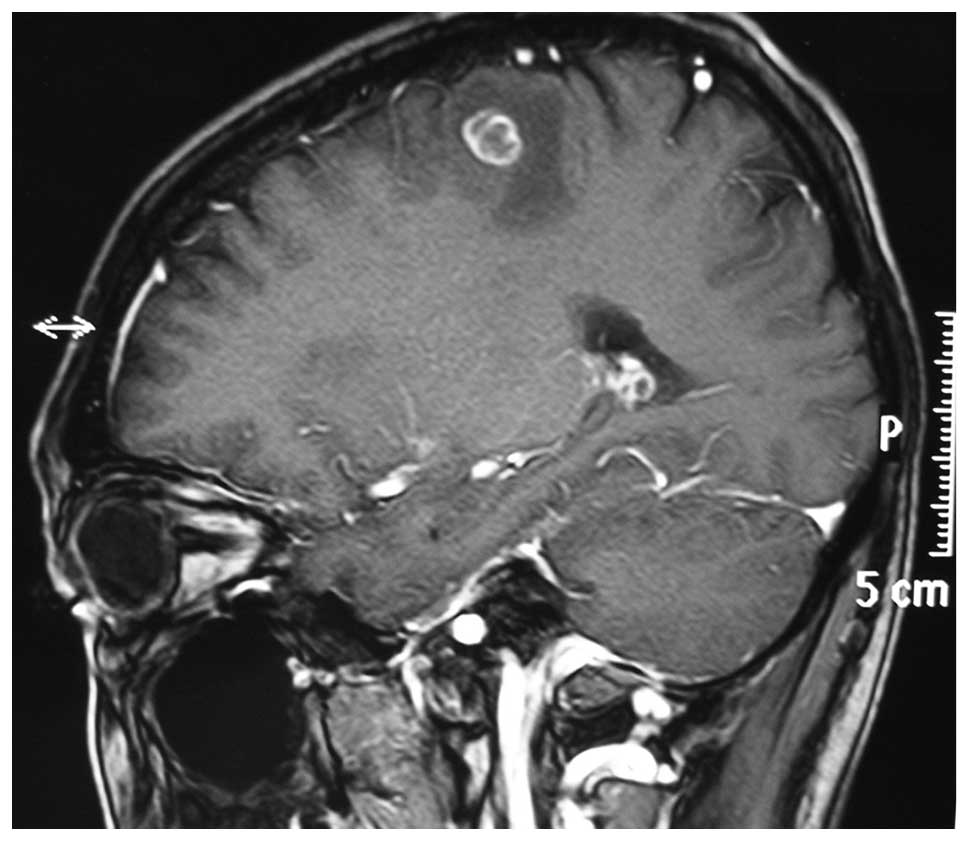

Treatment of pulmonary epithelioid hemangioendothelioma with combination chemotherapy: Report of three cases and review of the literature

No standard therapy for pulmonary epithelioid hemangioendothelioma (PEH) has yet been established due to the rarity of the disease, the lack of clear standards for treatment and the partial‑to‑complete spontaneous regression. This report describes three cases of PHE manifested as bilateral intrapulmonary masses with an initial diagnosis conducted by thoracoscopic lung biopsy. These patients demonstrated a partial response to combination chemotherapy with carboplatin, paclitaxel, bevacizumab or endostar, and an improvement in clinical status. Furthermore, we reviewed the literature regarding such patients who received chemotherapy and immunotherapy; this indicated that patients with PEH demonstrated a good partial response to chemotherapy with carboplatin, paclitaxel, bevacizumab, thalidomide and α‑interferon. Overall, combination chemotherapy regimens may hold therapeutic potential for the treatment of this rare disease.

Figure 2

Endo T, Su CC, Numagami Y and Shirane R: Malignant intracranial epithelioid hemangioendothelioma presumably originating from the lung: case report. J Neurooncol. 67:337–343. 2004. View Article : Google Scholar : PubMed/NCBI